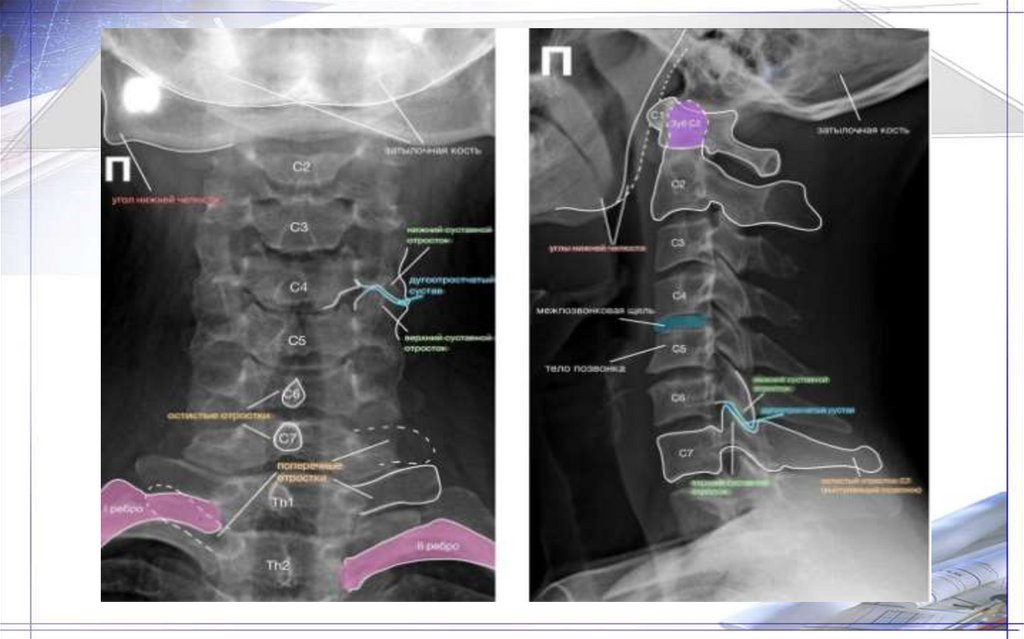

Рентгенограмма верхних

шейных позвонков в прямой

проекции

1. Ножка дуги шейного позвонка

2. Дуга осевого позвонка

3. Остистый отросток шейного позвонка

4. Боковые массы атланта

5. Зуб осевого позвонка

6. Верхняя суставная поверхность

второго шейного позвонка

7. Передняя дуга атланта

8. Задняя дуга атланта

Рентгенограмма шейного

отдела позвоночника в

прямой проекции

1. Межпозвонковое пространство

2. Полулунные отростки

3. Ножка дуги позвонка

4. «Боковые массы» тел позвонков

5. Дуга позвонка

6. Остистые отростки

7. Подъязычная кость

8. Щитовидный хрящ

Рентгенограмма шейного отдела

позвоночника в боковой

1. Атлант

2. Остистый отросток

3. Дуга позвонка

4. Ножка дуги шейного позвонка

5. Межпозвонковое пространство

6. Верхний суставной отросток

7. Нижний суставной отросток

8. Проекция позвоночного канала

9. Тело позвонка

10. Превертебральные мягкие ткани

11. Реберно-поперечные отростки шейного

позвонка